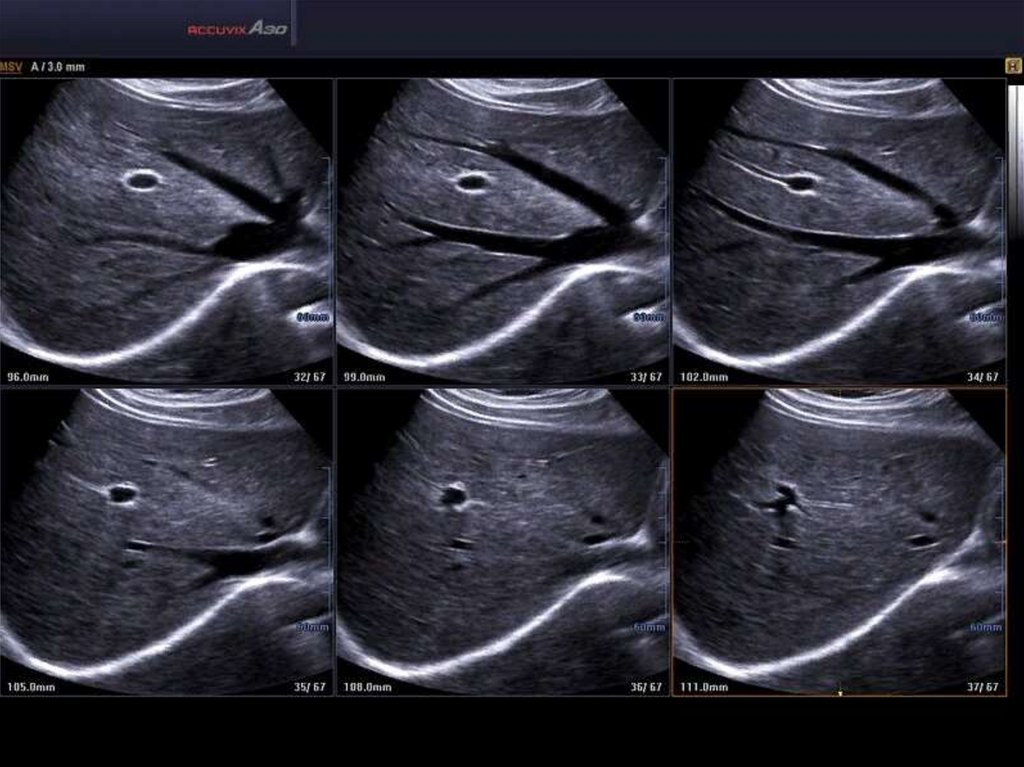

Видео ЭРХПГ, ЭПСТ, Литоэкстракция. 02:10 и далее на быстрой промотке

44. Видео ЭРХПГ, ЭПСТ, Литоэкстракция. 02:10 и далее на быстрой промотке

• https://www.youtube.com/watch?v=x9OceQh

cg-I